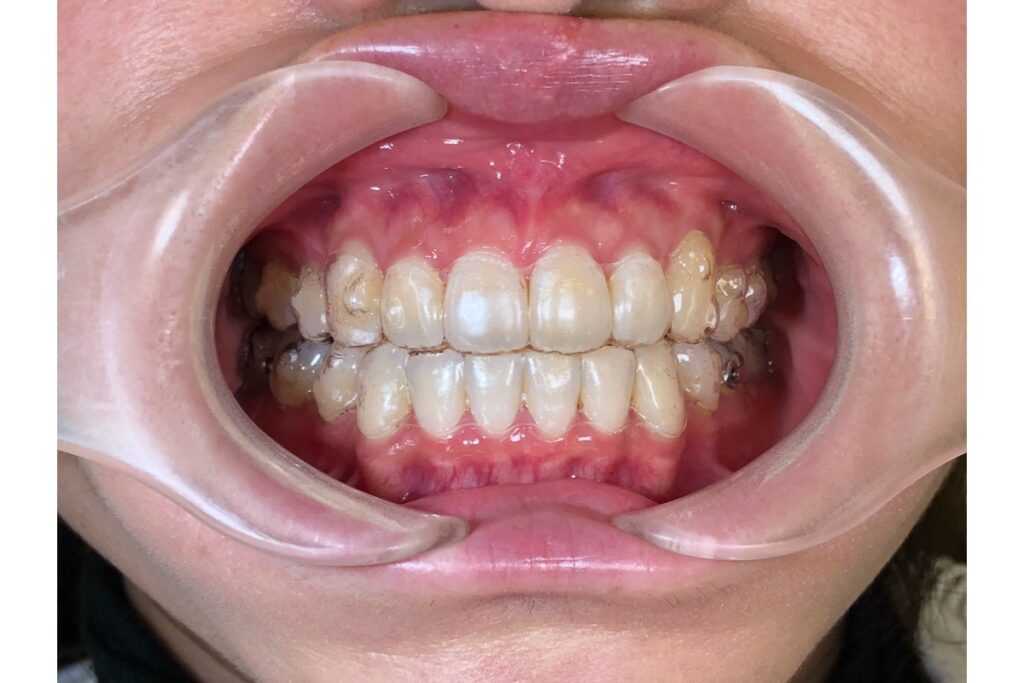

交叉咬合とは?

交叉咬合とは、本来は上の歯が下の歯の外側にあるべきところ、部分的に逆転している噛み合わせのことです。

つまり、「上下の歯が交差して噛んでいる」状態です。

前歯部交叉咬合前歯が反対(受け口のように見える)

臼歯部交叉咬合奥歯の一部が反対に噛んでいる(片側のみ多い)

片側性交叉咬合右または左のどちらかだけが反対に噛んでいる

中でも多いのは、片側性交叉咬合です。

左右どちらか一方だけで噛みやすいため、顔が歪んで見えることもあります。